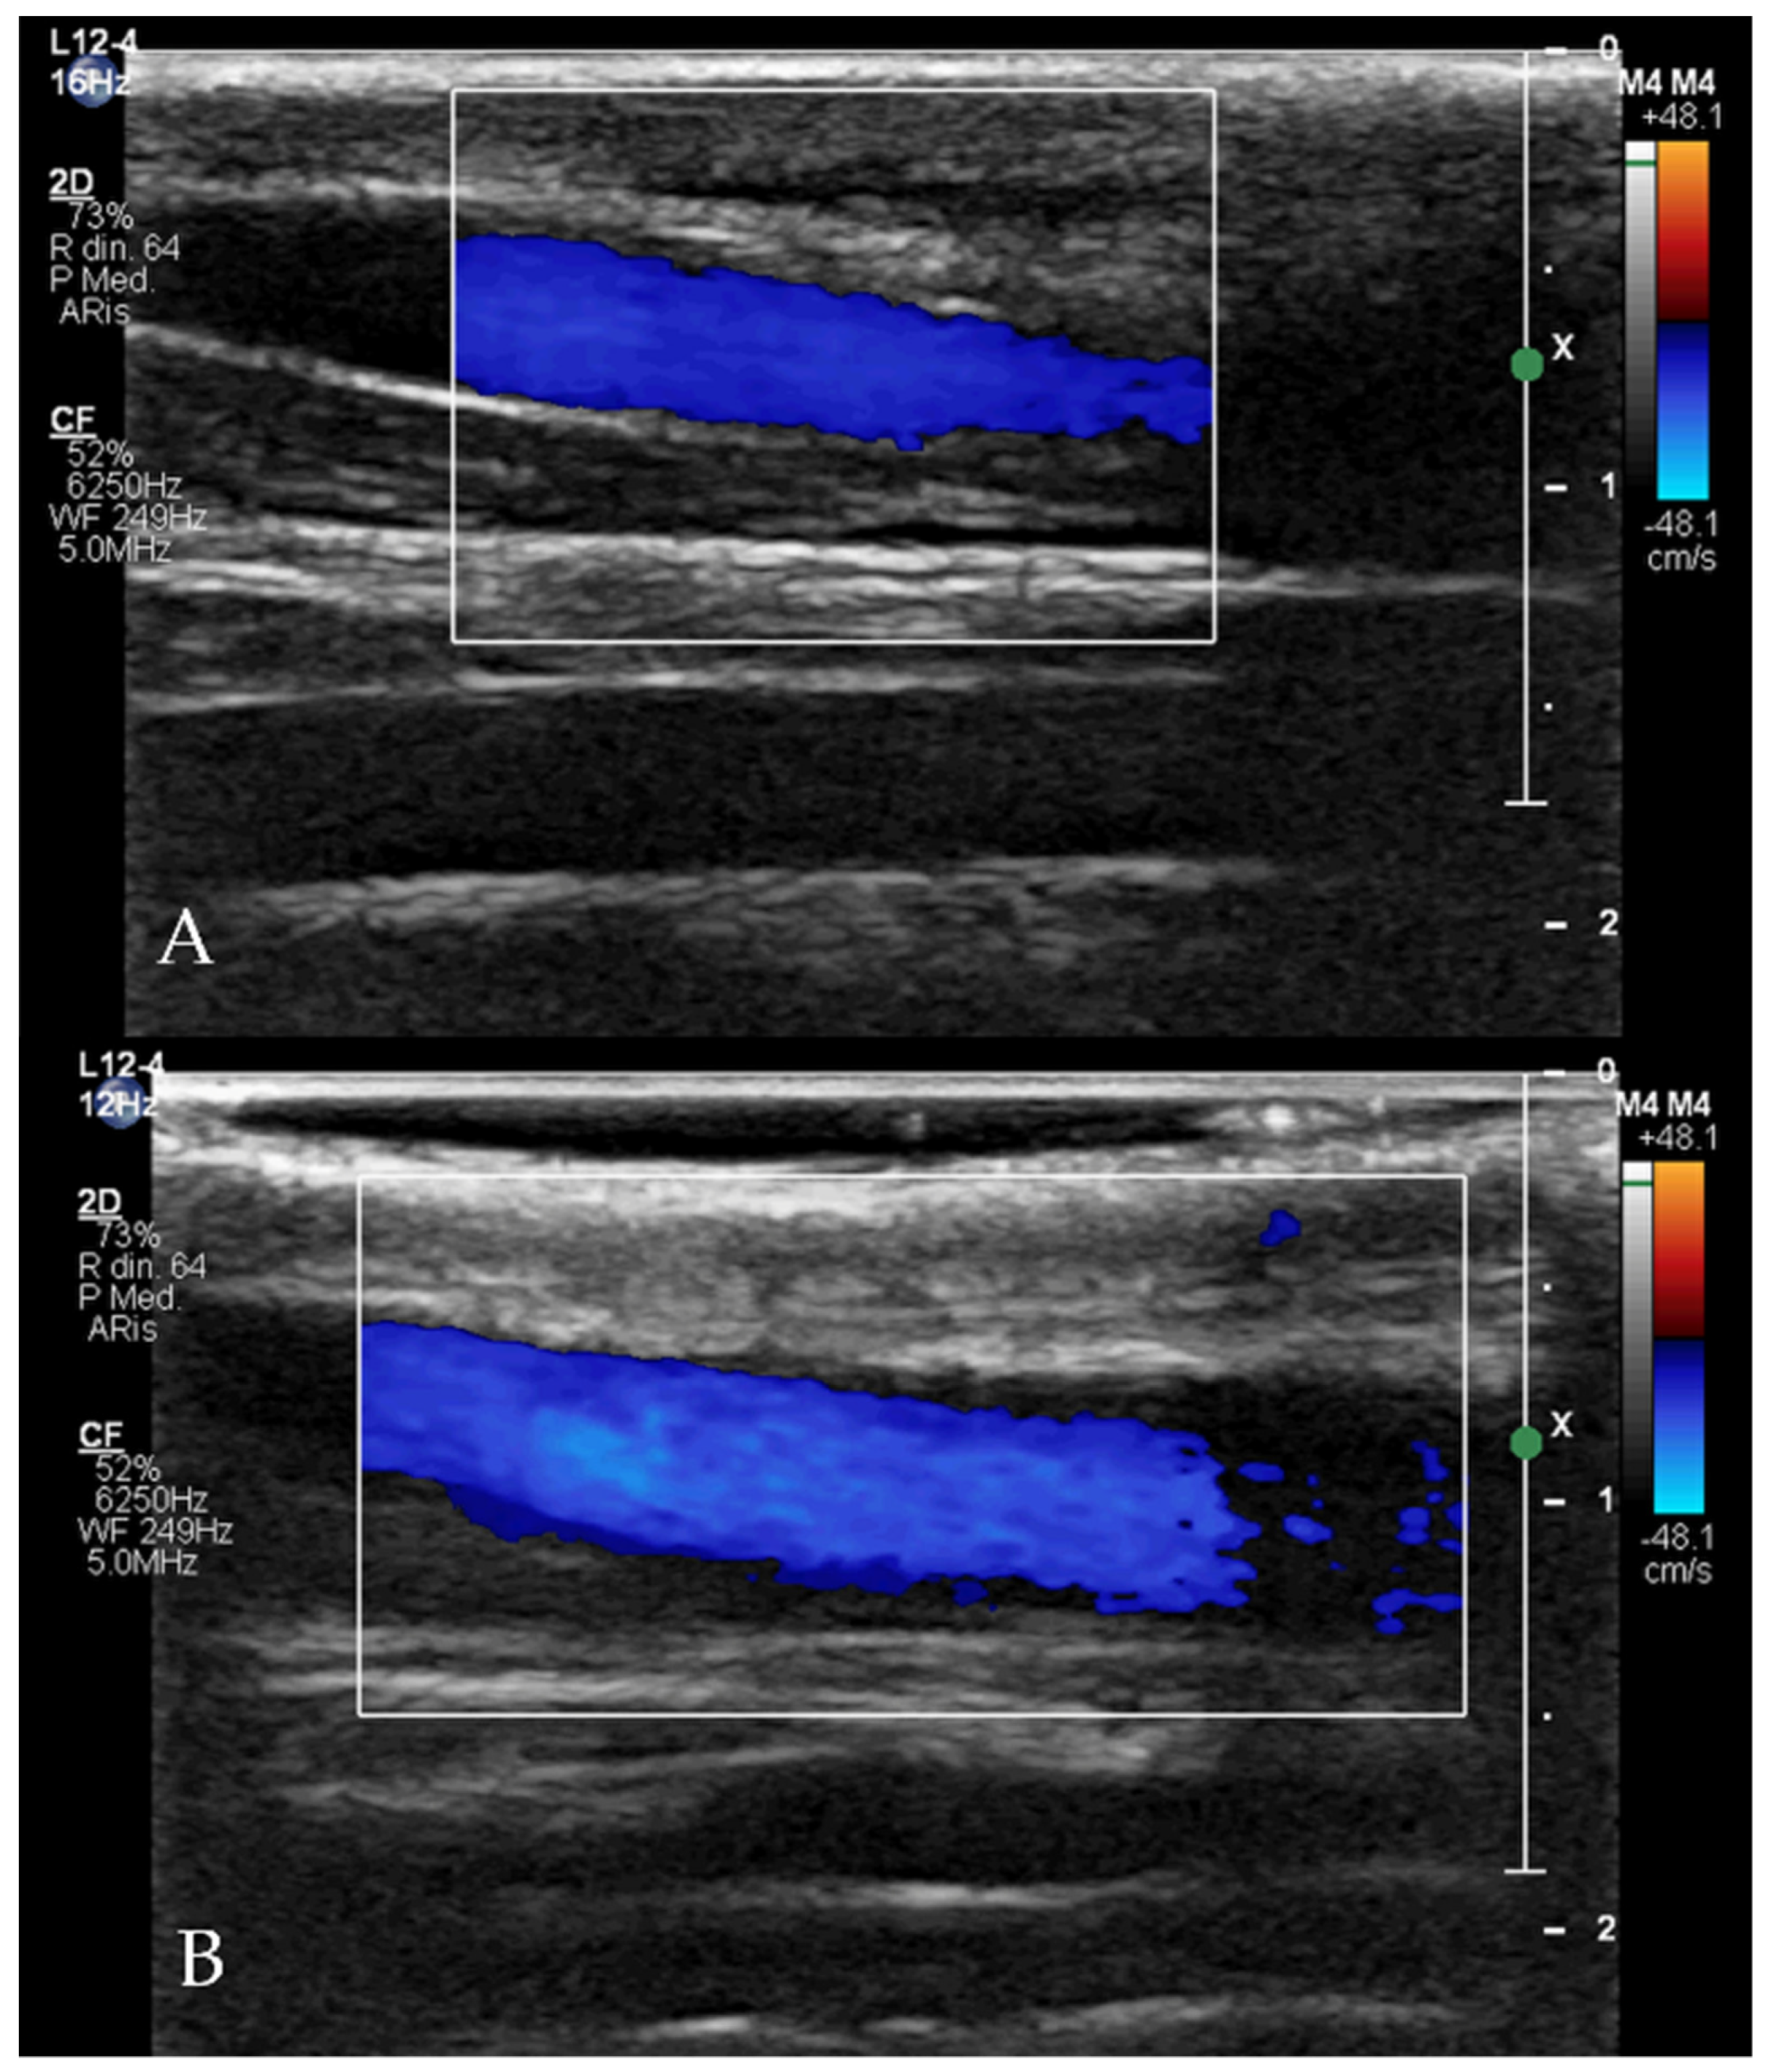

Clinical and echocardiographic check-ups were scheduled one day, one week, and three months after the procedure for all dogs. In all cases with the sutured jugular vein, the integrity of the vessel and flow normality were checked by vascular ultrasound.

The procedures were all performed as described in the Material and Methods with no complications. The total procedure time was between 20 and 45 min for all patients. After 24 h, the devices were visible within the ductus with no obvious extension into the pulmonary artery and no residual flow across the device in all dogs. The one-week and three-month echocardiographic examinations showed no residual flow across the device in any of the dogs. All patients showed a significant reduction in the left heart size after one week and three months (Table 2). Cases 3, 4, 5 and 6 were subjected to jugular vein suture and flows were normal three months after the procedure (Figure 7).

Figure 7. Doppler flow evaluation with linear probe (12 Hz) of the up (A) and down (B) jugular veins three months after the procedure (Case 5) demonstrating normal size of the right jugular vein compared to the left one, and normal flow within the vessel.